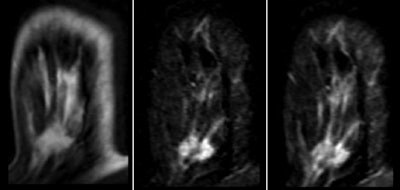

Overall, of the 108 lesions, 107 (99.1%) were correctly assessed as probably benign, for a negative predictive value of 99.1%. Histopathology was requested for 44 patients; 43 lesions (39.8%) were classified as benign and one (0.9%) as malignant. There were no changes evident in any of the remaining 64 (59.2%) lesions during the follow-up period, according to the authors.

Based on the findings, specific imaging features for BI-RADS 3 lesions at MRI -- such as round or oval shape, smooth or lobulated margins, and a type I or type II curve -- should be included in a new version of the BI-RADS lexicon, the team wrote.